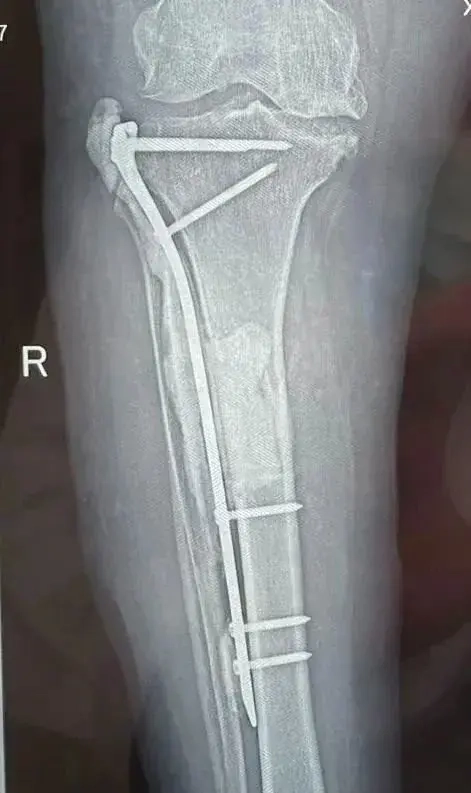

近日,西安市第五医院就接收了一例骨髓炎的患者。患者马女士,60岁,2月前无明显诱因出现了右小腿近端疼痛并活动受限,到西安某医院就诊,拍X线片后未发现有明显的异常表现,医院给她开具了口服止痛药物,但马女士服用四五天后感觉症状并没有缓解,仍然行走困难。听其所住小区朋友介绍说五院看“腿疼”看的好,心想我在大医院都没有看好,去五院能行吗?在马女士朋友的一再劝说下,马女士抱着试试看的心态前往西安市第五医院就诊,在骨科贺强副主任及其团队的仔细检查下,确诊马女士患的是右侧胫骨骨髓炎。

为了有效降低术后复发率并能够使马女士更快的康复,骨科贺强副主任团队决定给马女士使用全新的治疗骨髓炎技术——Masquelet骨诱导技术。

全新Masquelet骨诱导技术是近年来骨髓炎和慢性复杂创面的重要技术进步,该技术通过分阶段使用抗生素骨水泥填充、诱导局部成膜及自体异体骨移植,有效实现大范围骨与软组织缺损后的再生修复,解决了大范围骨与软组织缺损修复的技术难题。具有患者康复快,术后复发率低的优点。